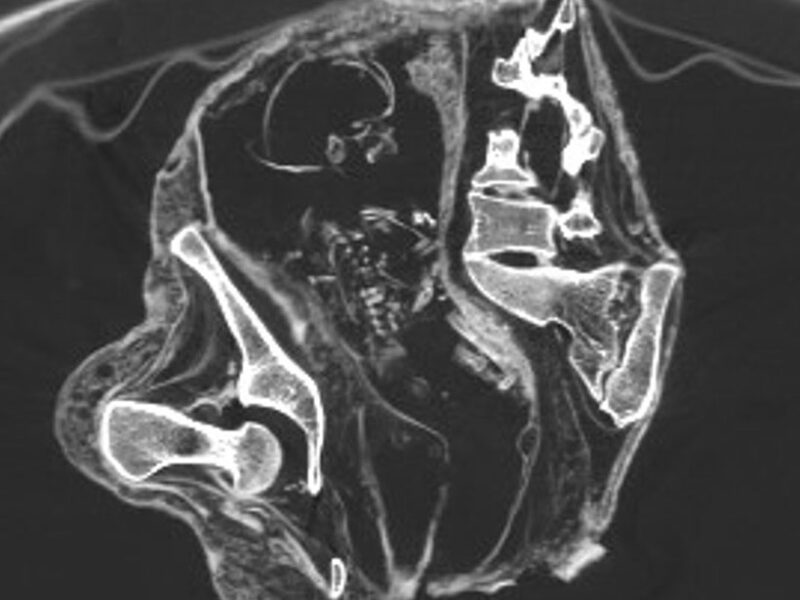

Анализ КТ-сканов двух мумий из Перу, часть 5

Беременность Монсерат Монсерат Когда Монсерат умирала, она была беременной — внутри неё находится ребёнок. Скрины КТ в кософронтальной плоскости — определяется голова плода со смещением костей черепа, рёбра и тела позвонков: По длине бедренной кости 43 мм можно судить о возрасте плода — около 30 недель. У плода ножное прилежание – в полости малого таза […]